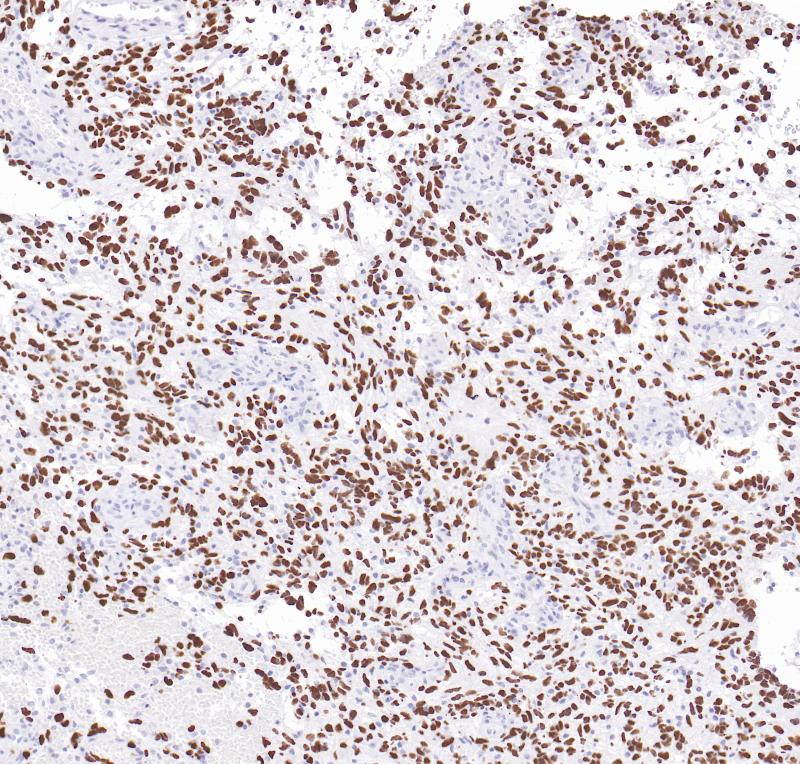

H3K27M突变可引起的H3K27低甲基化,影响基因转录稳定性,从而引起或促进癌症的发生与发展。H3K27M突变在老年胶质瘤和其他类型肿瘤极少或缺乏,在儿童和青年中线结构胶质瘤患者中显示出较为的独特模式,是恶性程度的一个标志,并且预示着预后较差和治疗效果差。

阳性对照

突变型弥漫性中线胶质瘤

亚细胞定位

细胞核